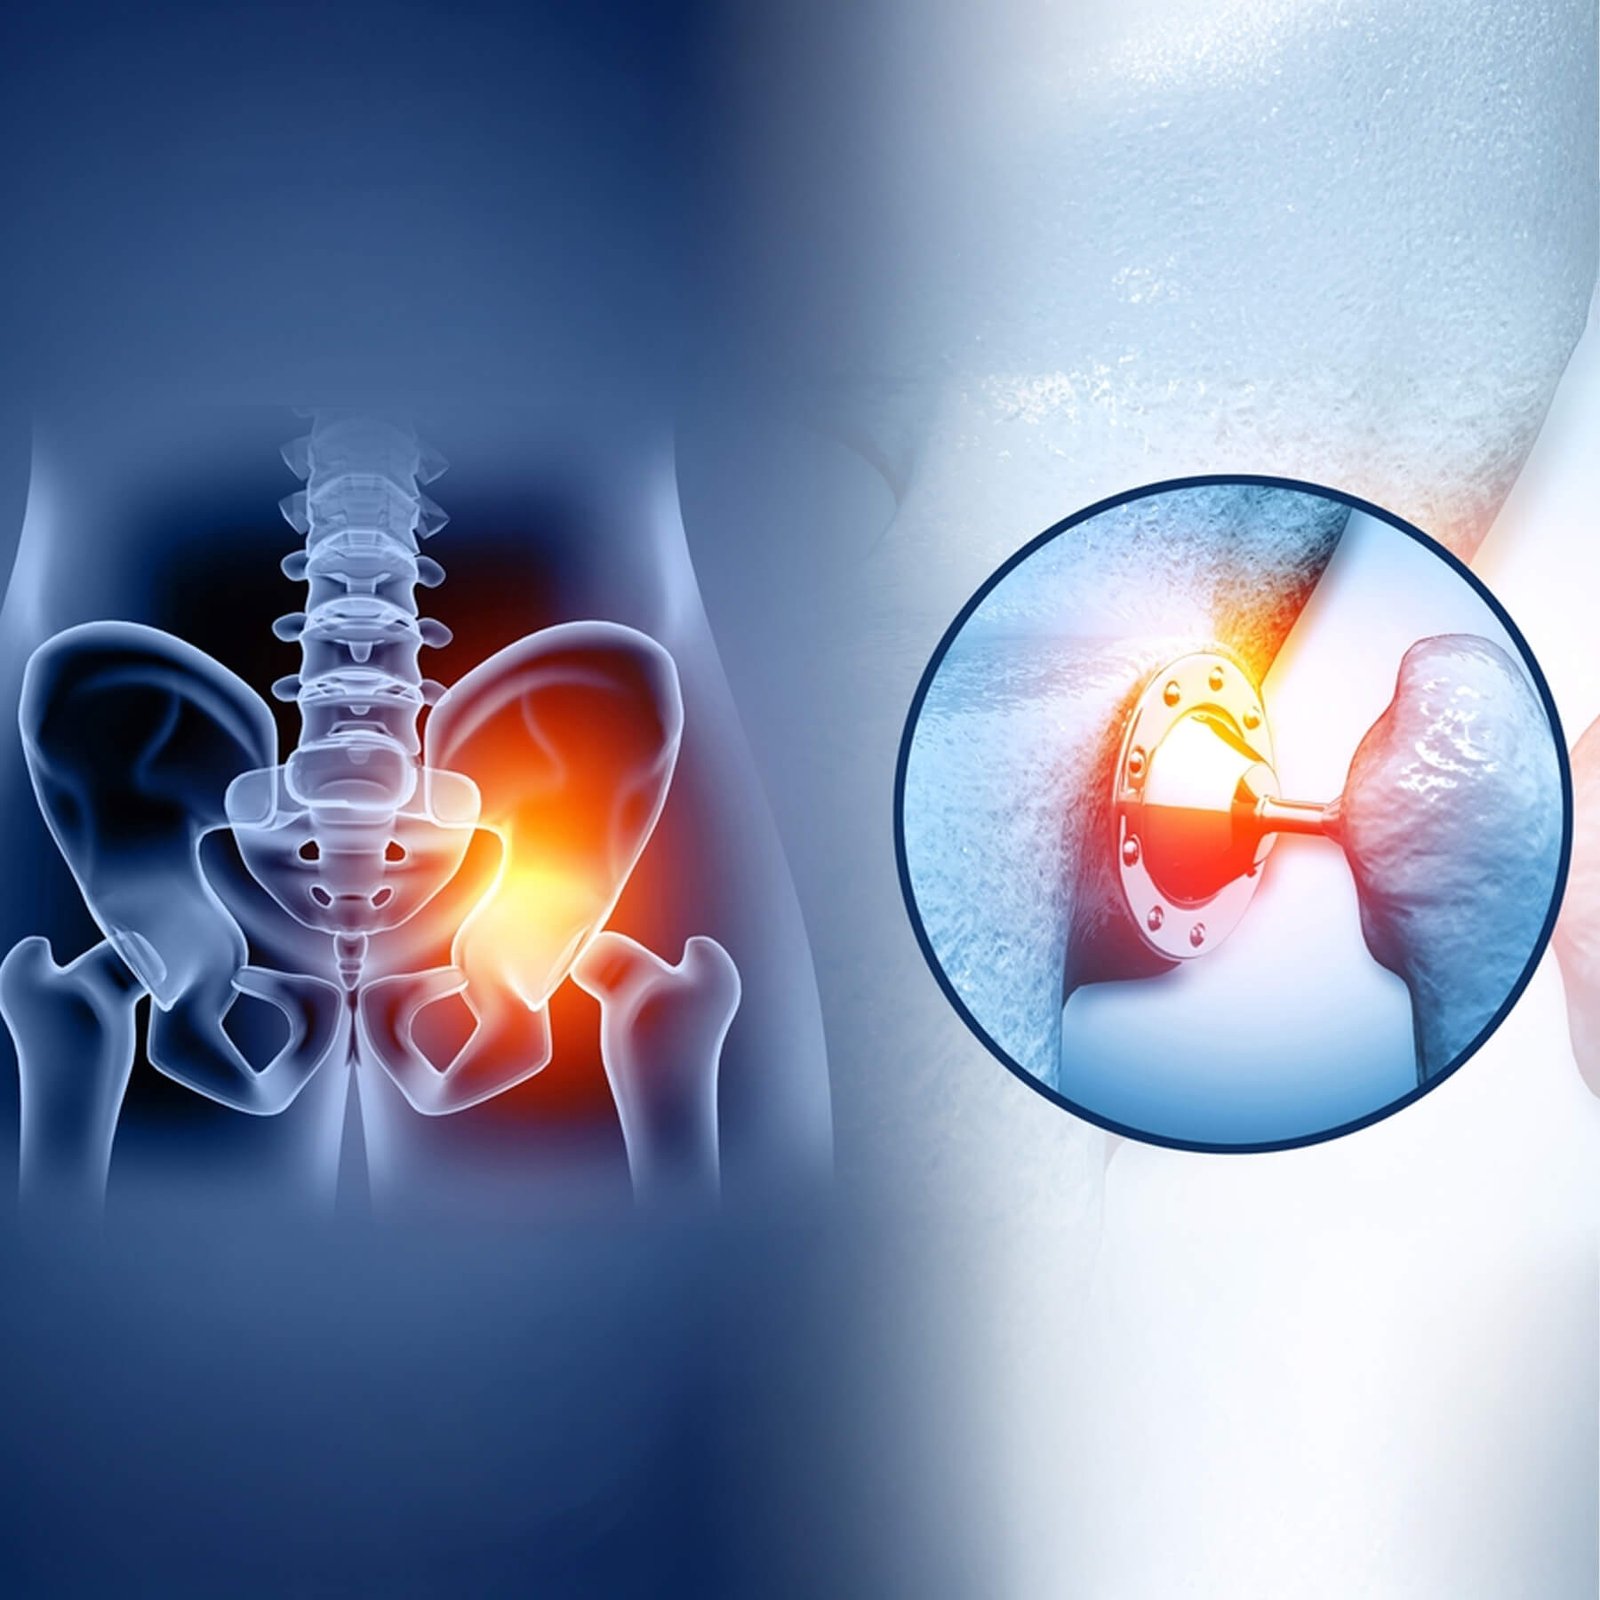

Hip Replacement Surgery

Comprehensive hip replacement surgery with advanced implants, restoring movement, reducing pain, and enabling patients to live active, pain-free lifestyles.